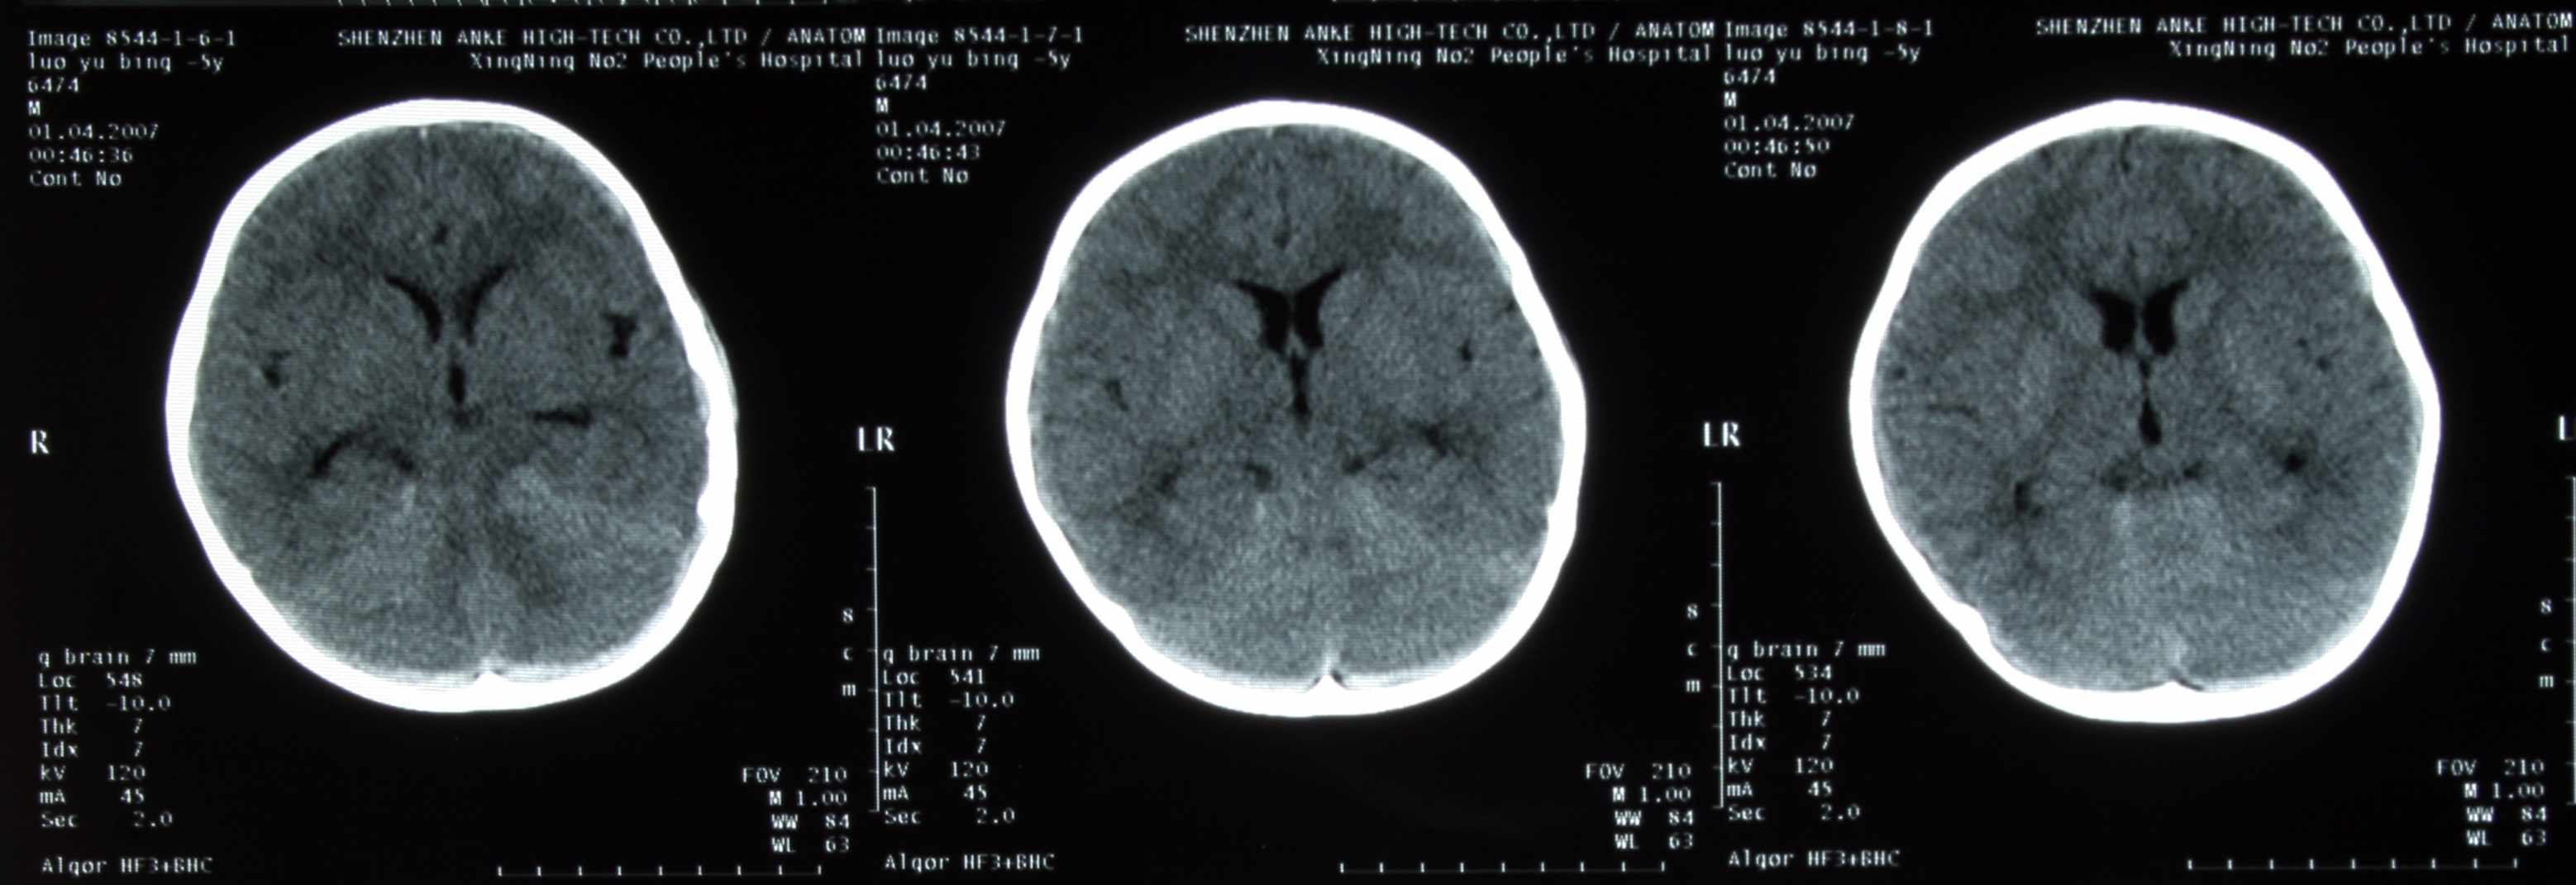

患儿,男,3周岁,半小时前不慎从床上摔下来,当时前额着地,后诉有点痛,伴呕吐二次,请各位老师会诊,患儿头颅有没有问题,后枕部颅下密度增高影,是伪影还是有出血,请指点:

支持后颅窝少量蛛网膜下腔出血。

后颅窝蛛网膜下腔出血。

小脑幕区蛛网膜下隙出血

支持后颅窝少量蛛网膜下腔出血,复查后便知。

后颅窝蛛网膜下腔出血